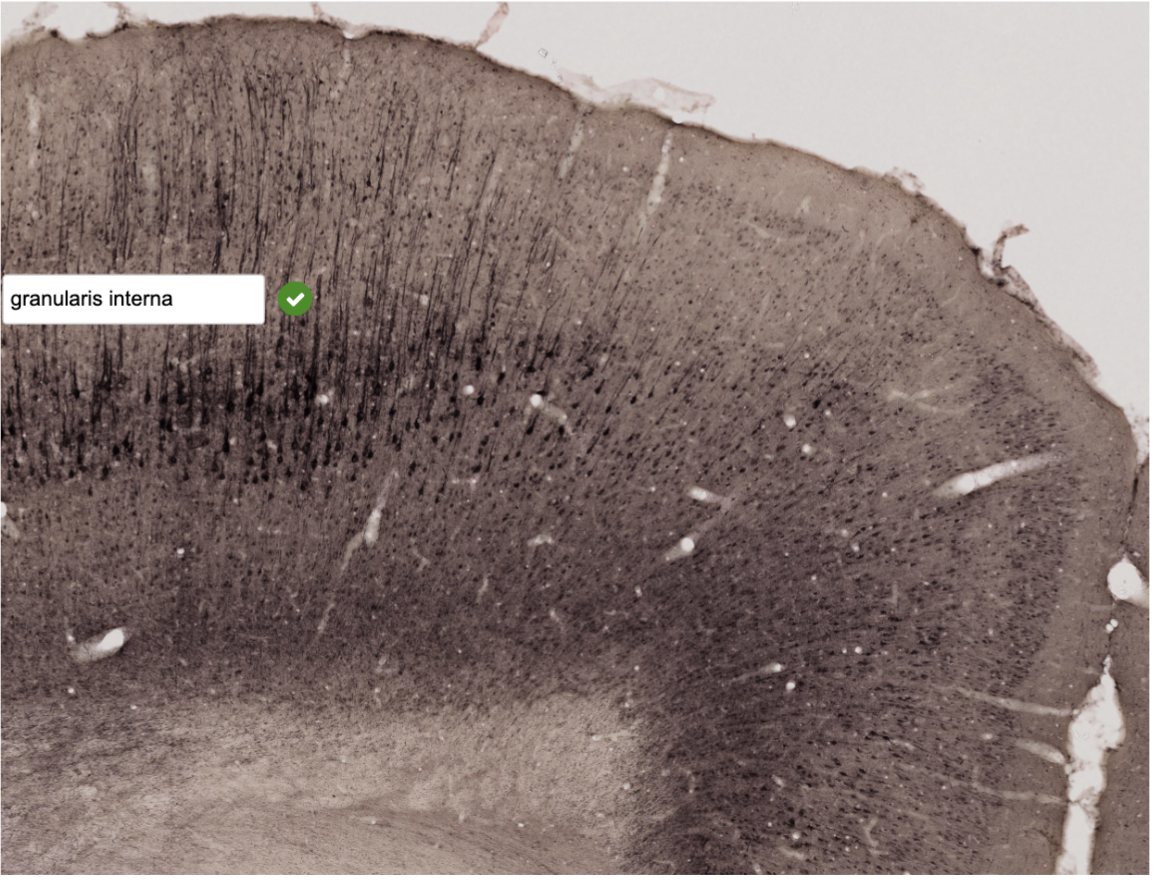

Bilden visar cortex i cerebrum (råtta). Rutan ligger i lamina … (fyll i resten) (1p)

granulis interna